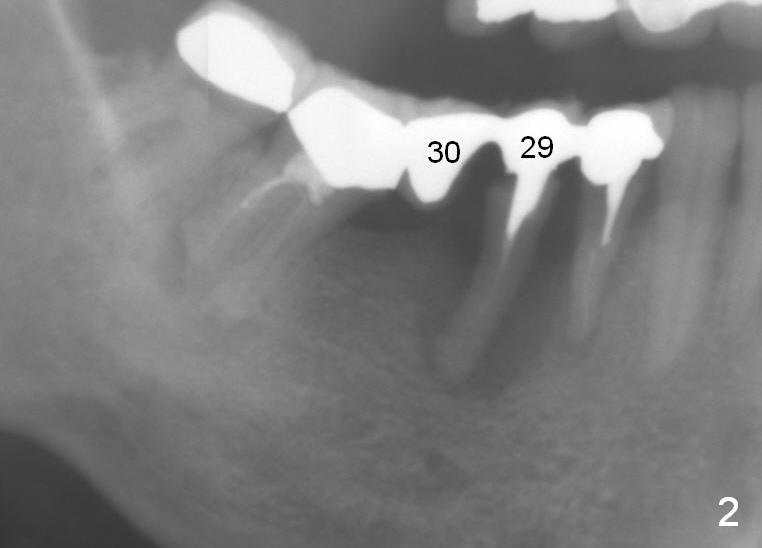

A 50-year-old lady (ZC) has poor dentition (Fig.1). The buccal gingiva of the tooth #29 is erythematous and edematous with deep pockets and severe bone resorption (Fig.2). Two units of the 5-unit bridge is going to be removed (Fig.3). A large implant is to be placed at the site of #29 (socket treated with Metronidazole), while a small one (probably 1-piece) at #30 (narrow mesiodistal space, Fig.4 green outlines). Be care of the mental loop (red dashed line). In fact, the patient wants to have #3 implant placed first.